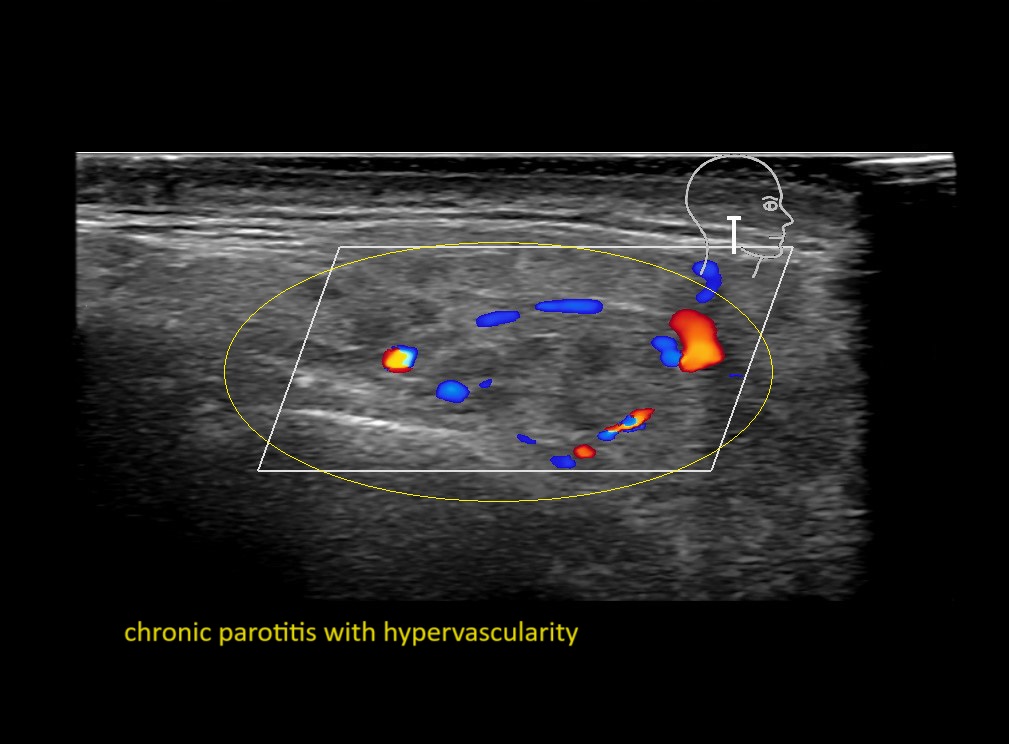

With ultrasound signs of inflammation can be visualized. Edema can be seen as a hyperechoic appearance of the subcutaneous fat, sometimes separated by hypoechoic fluid filled area’s, known as cobblestone appearance. Increased vascularization (hypervascularity) can be seen on colour Doppler. An abscess will appear as a fluid collection appearing as an irregular hypoechoic area with heterogeneous internal echoes and a thickened wall. Posterior acoustic enhancement can be present, and there is vascularity around but not within the mass. Under ultrasound guidance, abscesses can be managed by needle aspirations (18G) under antibiotic cover.

Study the first image to recognize the different layers. If you are sure about the layers, swipe to the second image to view the answer (if applicable).

Hover over an image to view the secondary image or click on the image title for more information.